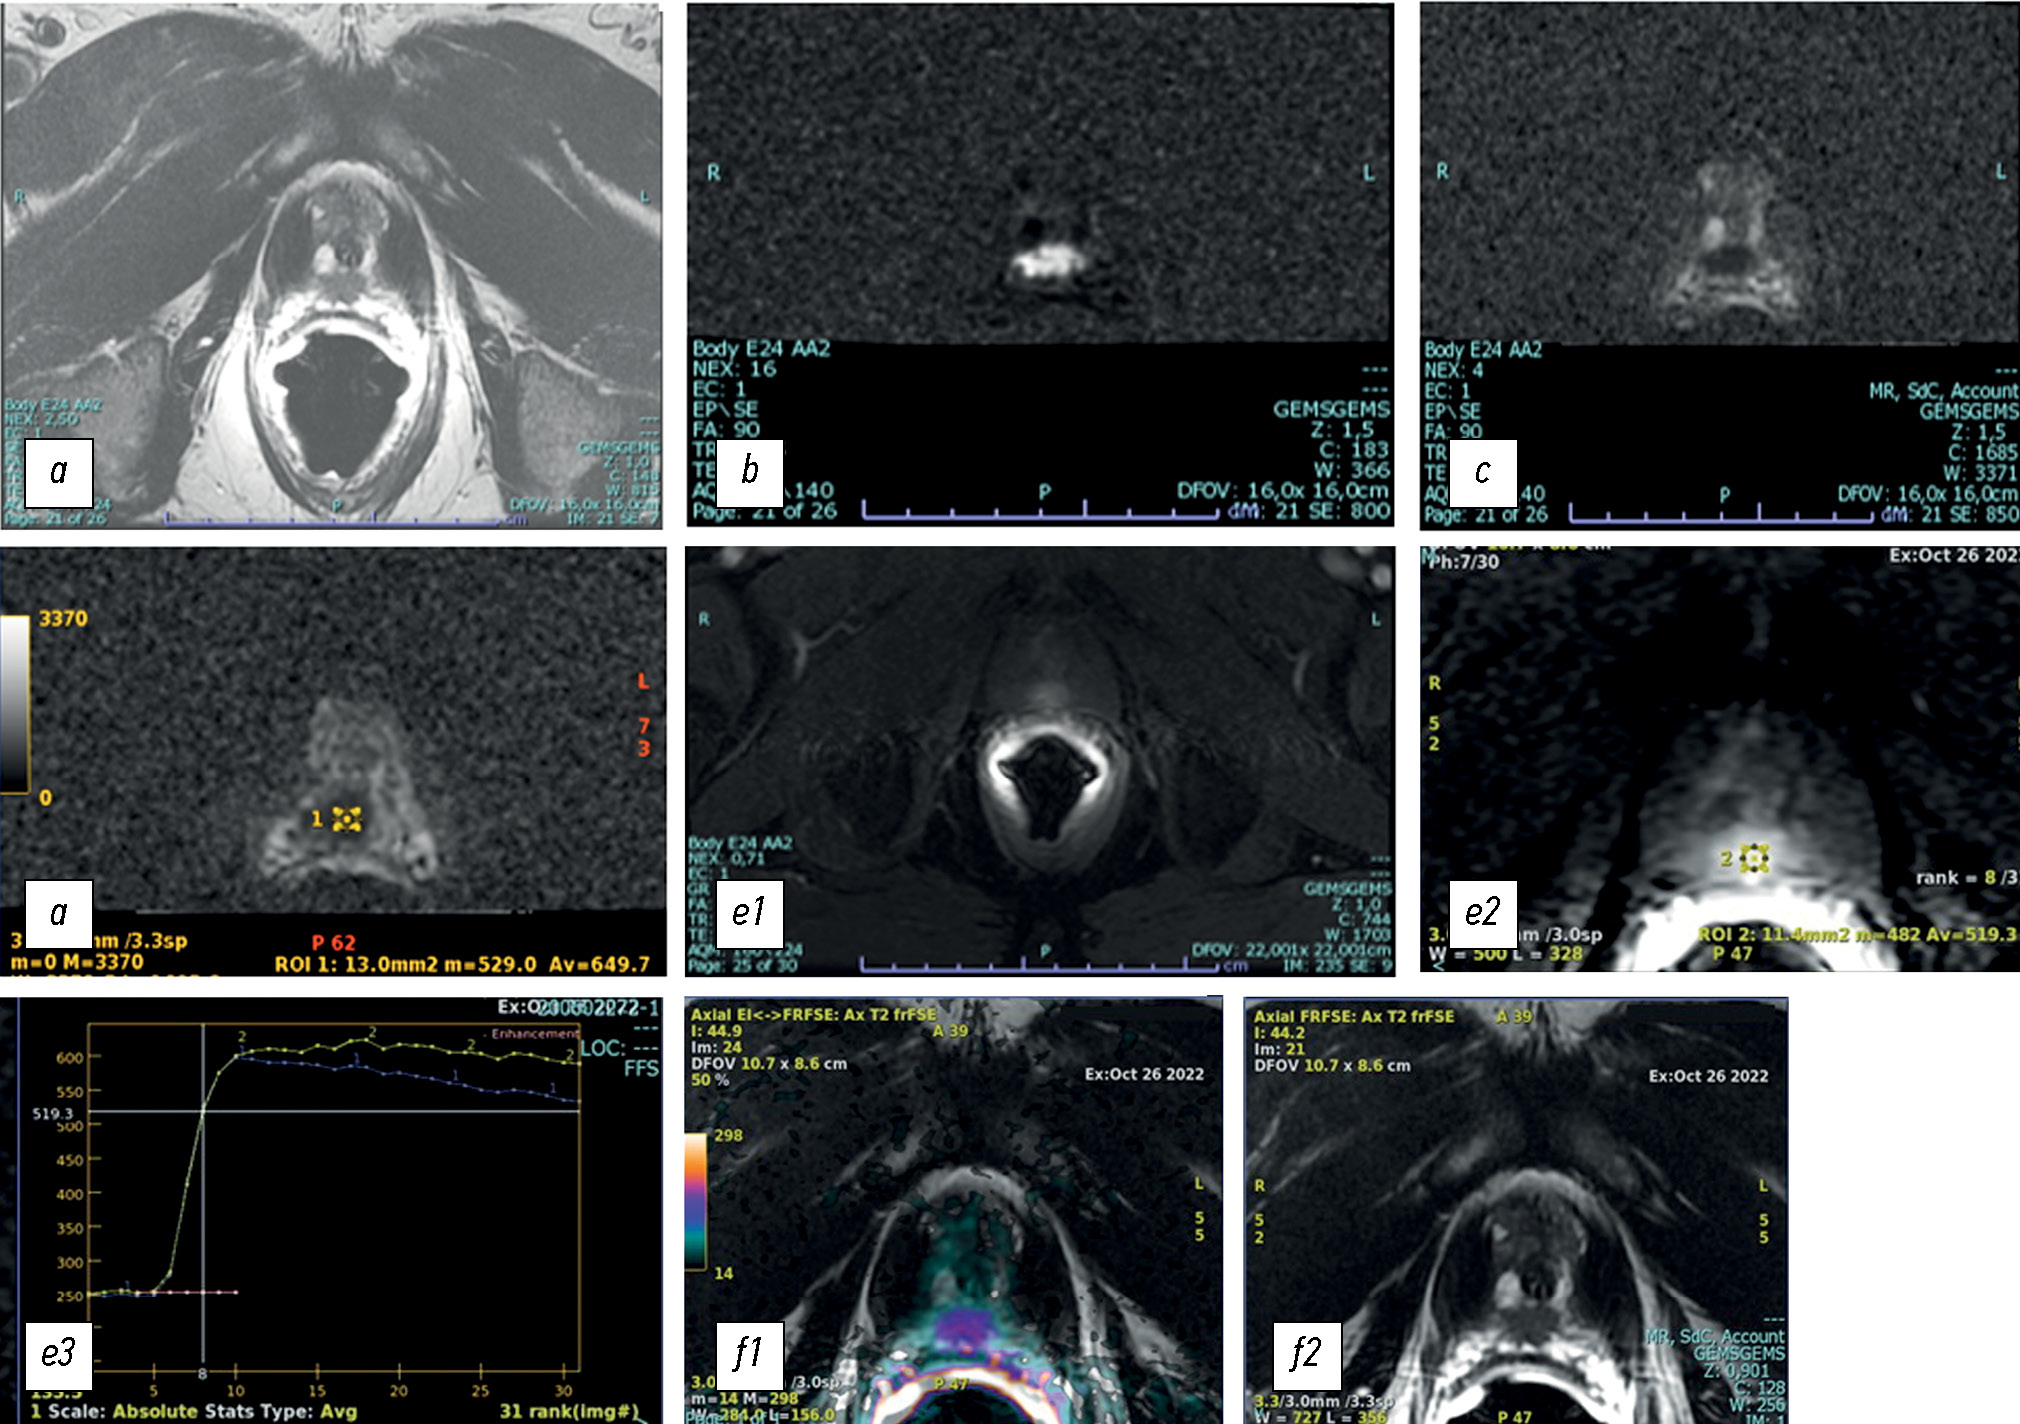

Возможности мультипараметрической магнитно-резонансной томографии при проведении фьюжн-биопсии под её контролем в диагностике рака предстательной железы: текущий статус

В данном обзоре освещается роль мультипараметрической магнитно-резонансной томографии в выявлении рака предстательной железы, в частности — при биопсии простаты. Использование мультипараметрической магнитно-резонансной томографии в диагностике рака простаты позволяет также применять её для биопсии. Мультипараметрическая магнитно-резонансная томография, по данным многих исследований, обладает высокой чувствительностью и специфичностью в ранней диагностике и стадировании у пациентов с сохраняющимся высоким уровнем простатспецифического антигена, несмотря на предыдущие отрицательные биопсии простаты, а также при ведении пациентов, находящихся под активным наблюдением.

Для проведения прицельной биопсии простаты существует три типа наведения: когнитивная фьюжн-биопсия; прямая биопсия, направляемая магнитно-резонансной томографией и выполняемая внутри томографа (in-bore); программная корегистрация снимков предоперационной магнитно-резонансной томографии с интраоперационным ультразвуковым исследованием с помощью фьюжн-устройства. При этом при проведении прицельной биопсии результаты мультипараметрической магнитно-резонансной томографии накладываются в цифровом виде на изображения трансректального ультразвукового исследования в реальном времени.

Каждый метод имеет свои преимущества и недостатки. Прицельная биопсия с помощью магнитно-резонансной томографии улучшает качество гистологических результатов по сравнению с другими подходами, выявляя значимые индексные поражения с точностью до 90%. Правильное стадирование позволяет выбрать оптимальные варианты лечения, адекватно оценить прогноз, снизить частоту новых биопсий и осложнений. В настоящее время главная задача состоит в том, чтобы сделать биопсию в сочетании с магнитно-резонансной томографией более доступной и стандартизировать технику проведения процедуры, что позволит минимизировать межоператорскую вариабельность в зависимости от используемой системы.